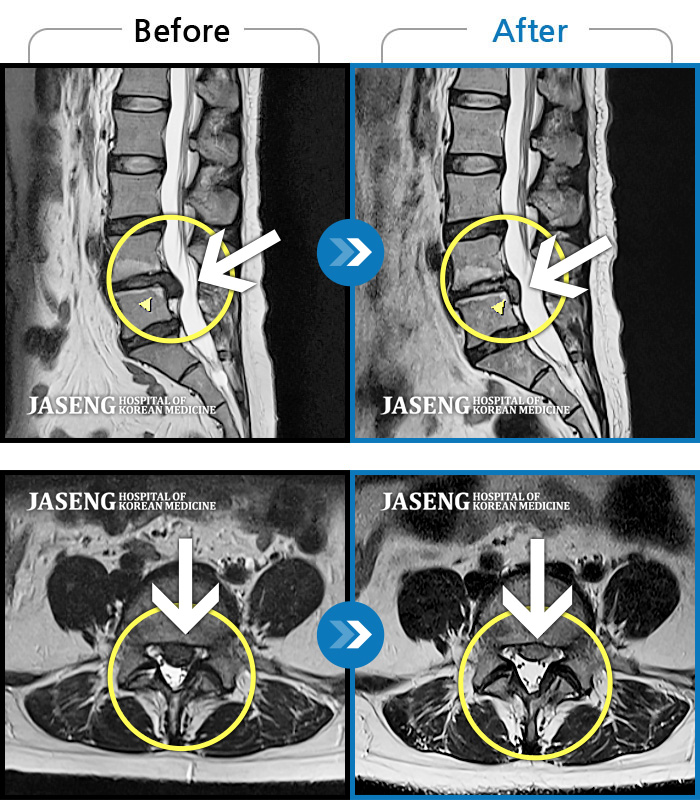

허리디스크

광주 · 장영우 원장

허리 좌측 골반에서 좌측 발까지 통증

촬영시기

2019.06.07 ~ 2019.12.04

2019.12.13